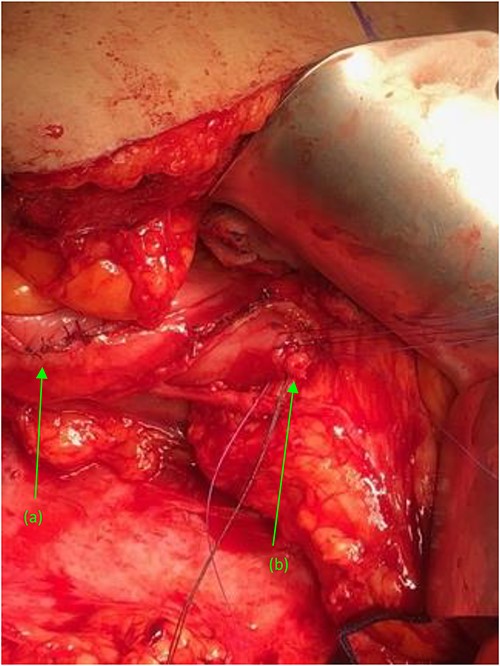

Two suture tagged fistulas status post fistulectomy and debridement to their base, entering the (a) second and (b) third portions of the duodenum, status post nephrectomy.

(a) Repaired duodenal defect where the (first) fistula previously entered the second portion of the duodenum, status post fistulectomy and stump closure. (b) Second fistula indicated by suture tags status fistulectomy and trimming to the base of the fistulous tract, near its entry point at the third portion of the duodenum.